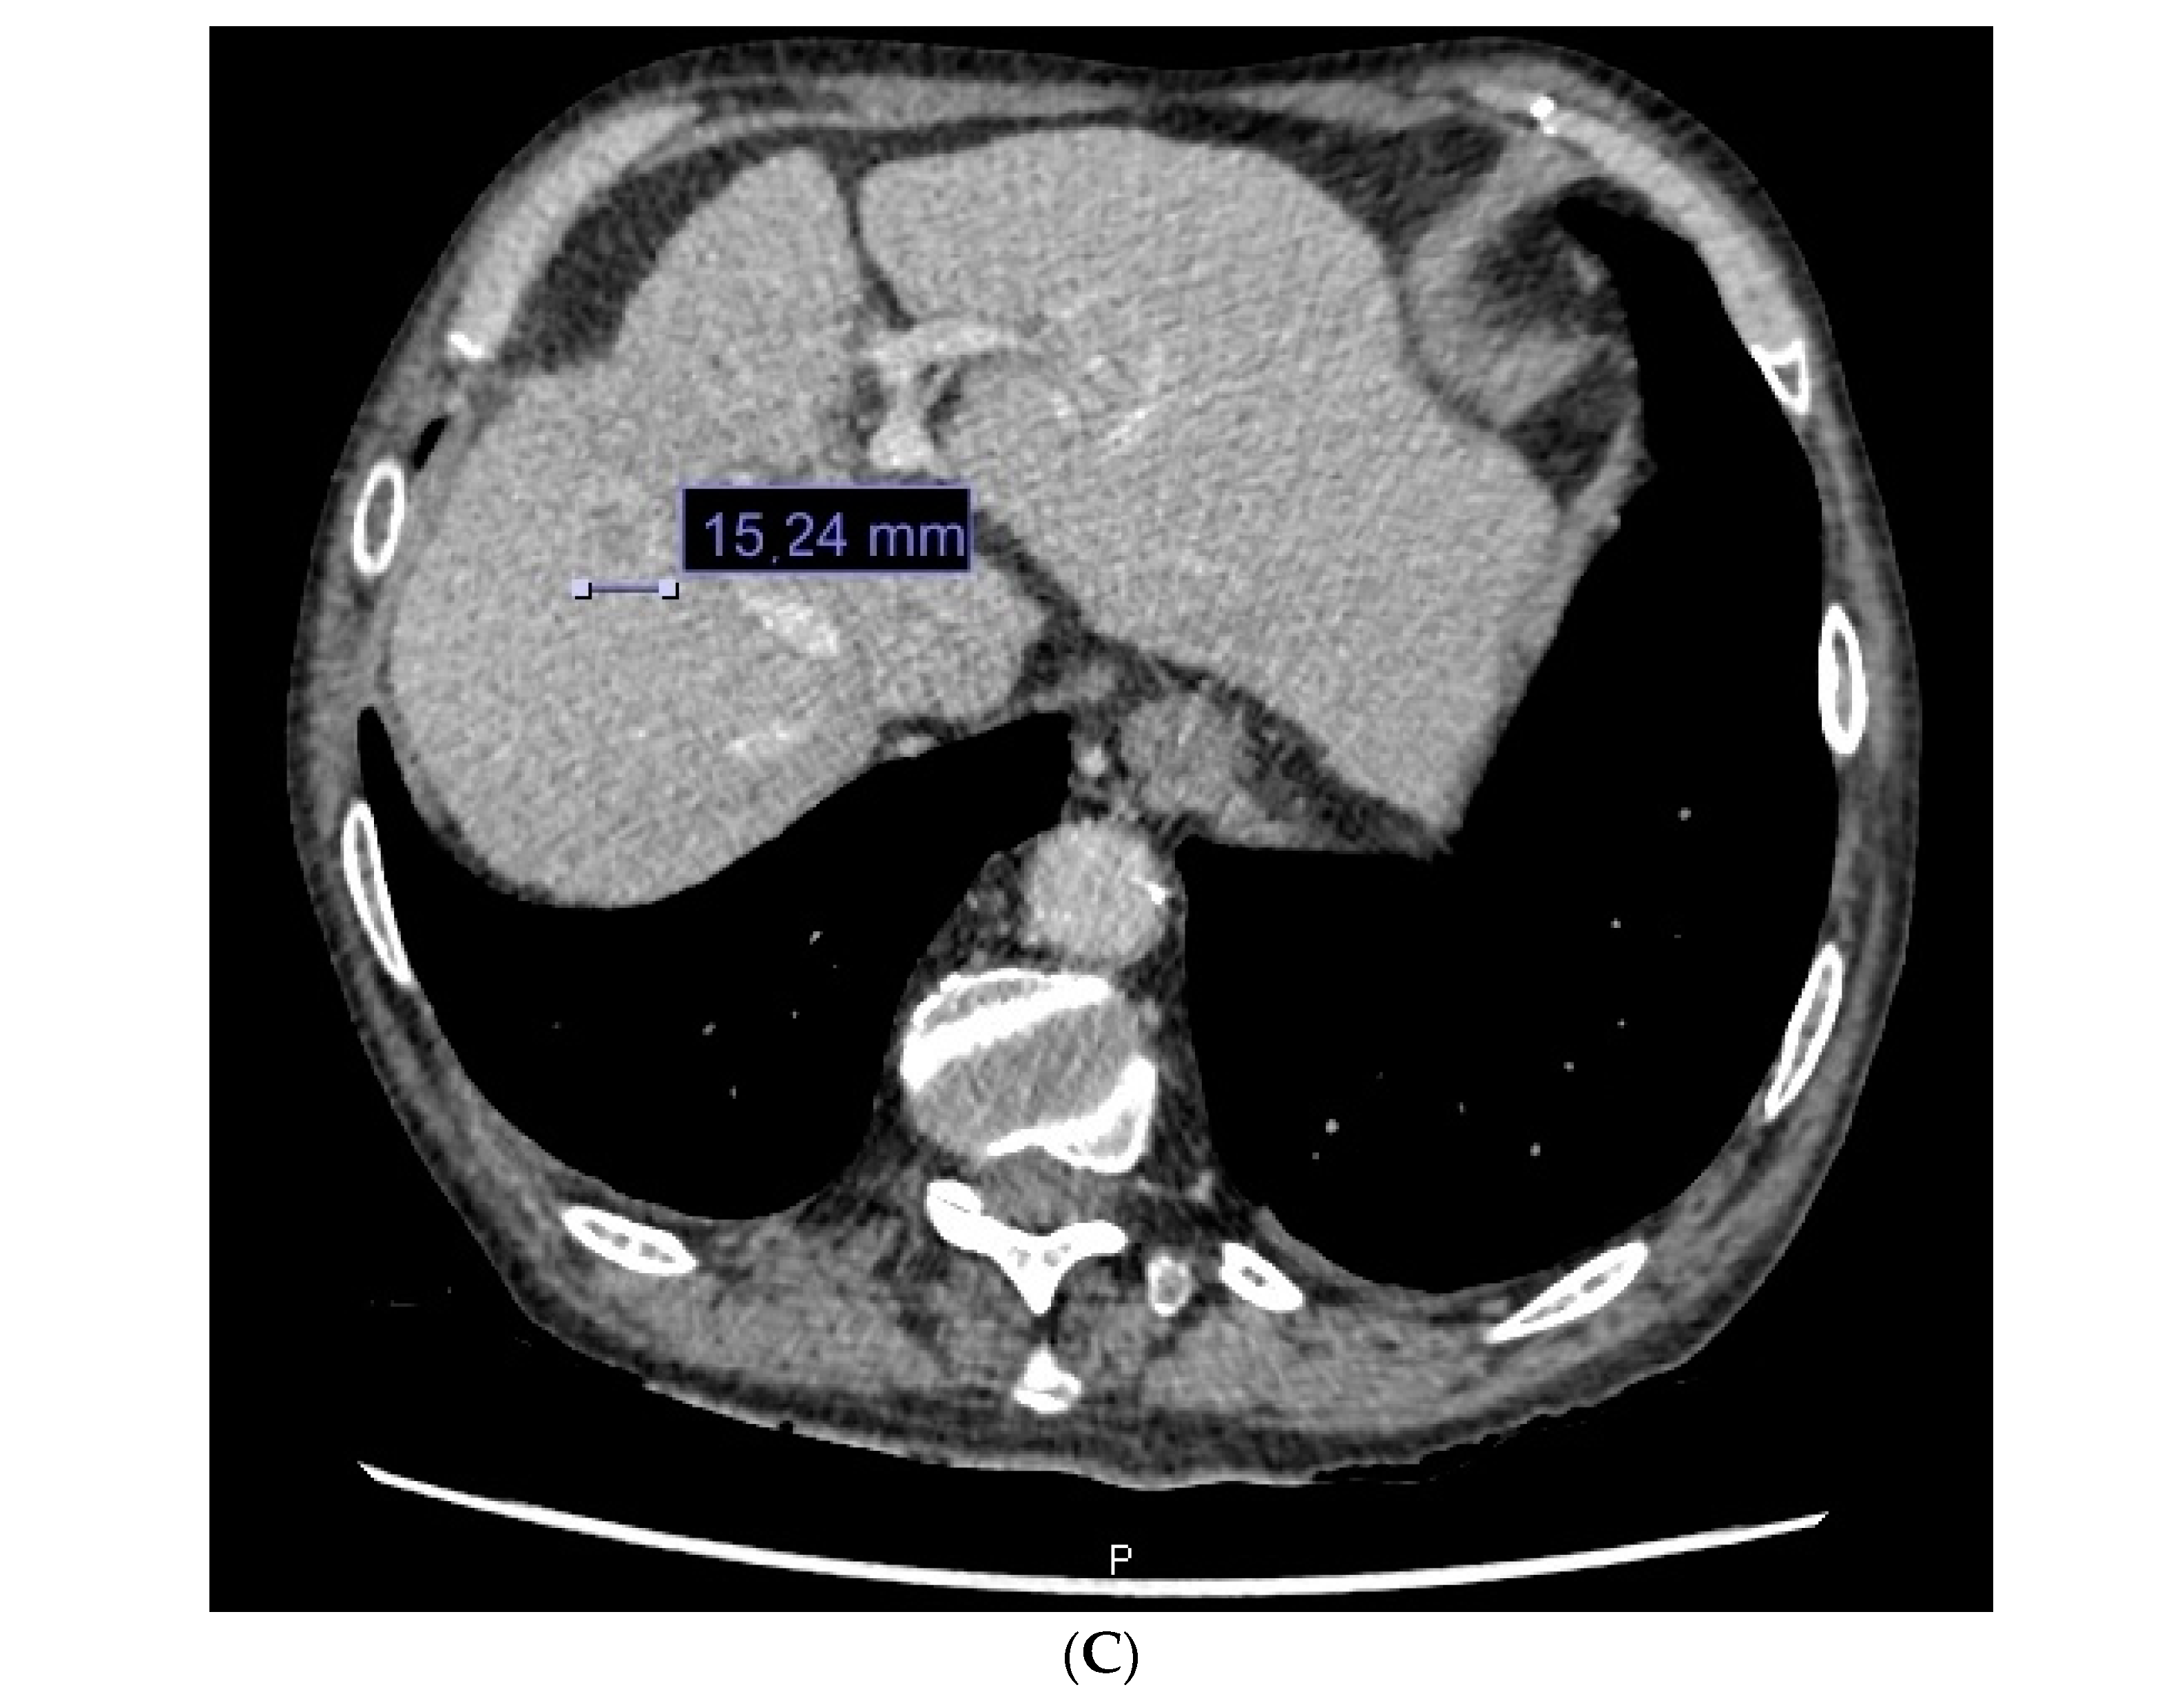

| Diagnostic method | Biopsy | 54 (33.33%) | 16 (55.17%) |

| Imaging test | 108 (66.66%) | 13 (44.87%) | |